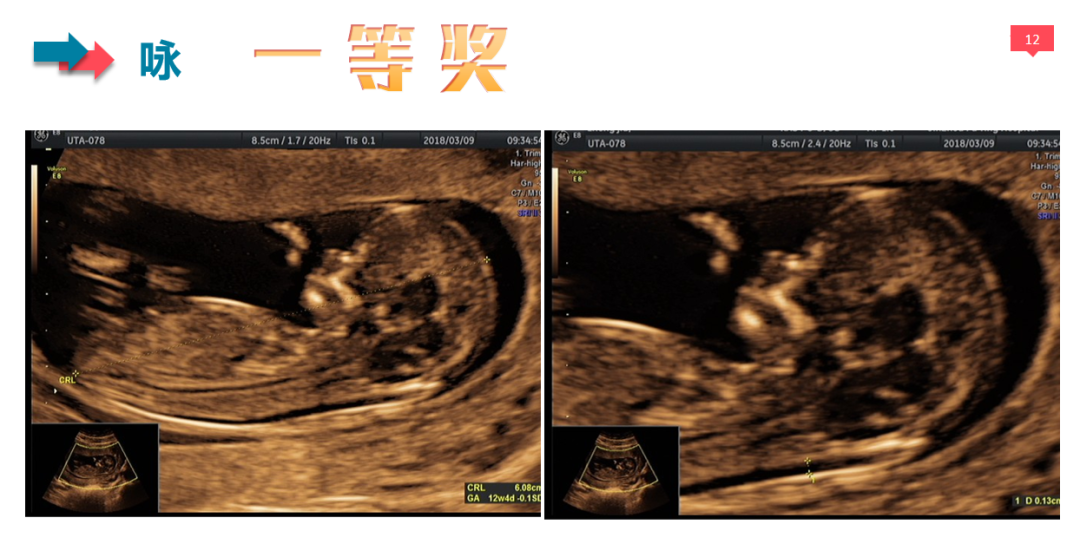

本次大赛共有26名医生参赛,分为I级检查、II级检查、III级检查和NT检查共4个组别,参赛医生上交3~15张图片不等,为了保证比赛的公平公正,评选采取盲评的方式,医生提交参赛作品时不使用真实姓名,而是被赋予毛主席的《卜算子·咏梅》中的一个字作为编号。

经过5位评委的独立评审和2位主任的审核,每组评选出6个作品进入更为严格的第二轮评选,第二轮评选由全体评委及审核共同对入围作品的得分点及扣分点进行逐一商确,最终每个组别分别评选出一等奖1名,二等奖2名,三等奖3名。